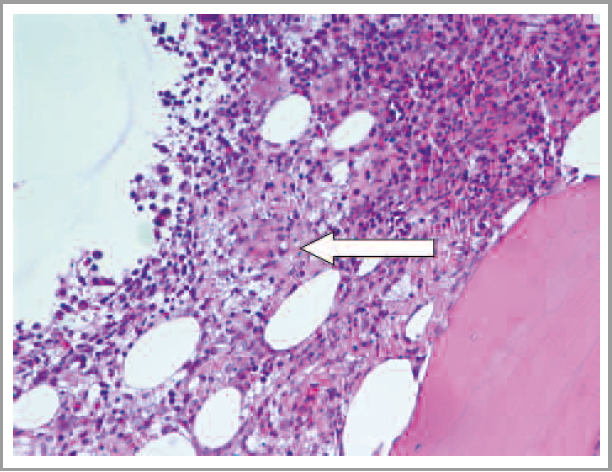

В апреле 2019 г. пациент госпитализирован в Университетскую клиническую больницу №3 ФГАОУ ВО «Первый МГМУ им. И.М. Сеченова» (Сеченовский Университет). Сохранялись гектическая лихорадка с проливными потами, выраженная общая слабость, желтушность кожи и склер; за весь период заболевания масса тела снизилась на 25 кг. При лабораторном обследовании, несмотря на продолжение терапии глюкокортикостероидами, отмечались значительное повышение уровня С-реактивного белка до 40 мг/л (норма до 5), признаки цитолиза и холестаза [АСТ – 262 ед/л (норма до 40), АЛТ – 207 ед/л (норма до 40), общий билирубин – 52 мкмоль/л (норма 3–21), прямой билирубин – 38 мкмоль/л (норма до 5), ГГТ – 1198 ед/л (норма до 73), ЩФ – 1982 ед/л (норма 70–360)]. Также обращали на себя внимание снижение уровня альбумина до 22 г/л (норма 35–52), при отсутствии других признаков снижения синтетической функции печени (протромбиновый индекс 98%), умеренная лейкопения (3,5 тыс/мкл), снижение уровня тромбоцитов в динамике (с 750 тыс/мкл после спленэктомии в декабре 2018 г. до 250 тыс/мкл в апреле 2019 г.). На основании серологического исследования исключены бруцеллез и туляремия. Пересмотрены гистологические препараты печени, внутрибрюшного лимфоузла и трепанобиоптат костного мозга, выявлены лимфо-макрофагальная инфильтрация портальных трактов, очажки коагуляционного некроза в паренхиме и строме печени без выраженной воспалительной инфильтрации с признаками кариорексиса (рис. 1, см. на цветной вклейке); гистиоцитоз синусов лимфатического узла, в цитоплазме отдельных макрофагов – мелкие базофильные включения неправильной формы; в трепанобиоптате костного мозга обнаружены макрофагальные гранулемы (рис. 2, а, см. на цветной вклейке), признаки угнетения эритроидного ростка, продуктивного васкулита и мелкие очажки коагуляционного некроза со слабой воспалительной инфильтрацией, признаками кариорексиса (рис. 2, б, см. на цветной вклейке), что в совокупности с клинико-лабораторными данными позволило заподозрить наличие висцерального лейшманиоза. Проведено серологическое иммуноферментное исследование, выявившее антитела к лейшманиям. Для подтверждения диагноза в ФБУН «ЦНИИ эпидемиологии» выполнено ПЦР-исследование крови и трепанобиоптата костного мозга пациента, выявившее ДНК Leishmania spp. (тест-система «АмплиСенс® Лейшманиозы-FL»). Пациент консультирован паразитологом и инфекционистом, рекомендована этиотропная терапия. После начала лечения отмечен быстрый положительный эффект в виде стойкого снижения температуры тела, улучшения лабораторных показателей.

Рис. 2. б - В трепанобиоптате костного мозга определяются мелкие очажки некроза со слабой воспалительной инфильтрацией, признаками кариорексиса. Окраска гематоксилин-эозином, *200